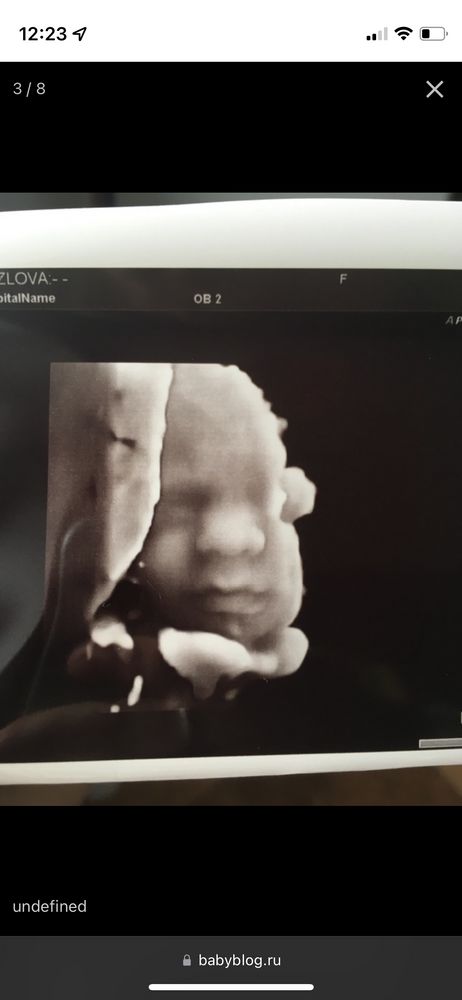

🏥 Сегодня была на узи 😁Совершенно не волновалась, но смотрели меня минут 30 🙈и так крутили и так. Малыш совсем не хотел показывать личико, зато писюн с радостью 🤣мельком мне его показали (красавчик 🥰), а фотку сделать не дали 😔

👶Весит малыш 320 г, срок ровно 20 недель, все в норме 🥳шейка 4 см 💪🏻